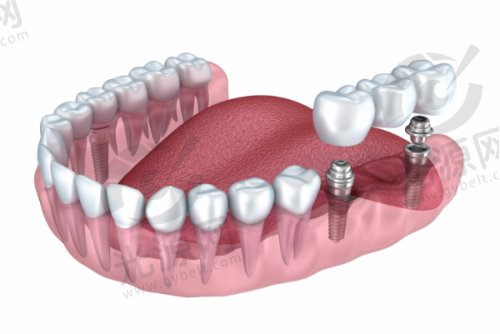

二、诺贝尔种植牙的技术优势与医生水平

诺贝尔种植牙在技术上引入了领跑的微创手术理念,较大限度减少患者的疼痛和术后修复时间。医院的种植牙医生均接受过专精的国内外培训,并持有相关资质证书。例如,诺贝尔的Active系列种植体因其独特的螺纹设计和亲水性表面,能与骨组织快速结合,提供出色的初始稳定性,极大提高了种植成功几率。此外,医院根据每位患者的具体情况,制定个性化的种植方案,确保治疗的针对性和有效性。特别多患者在接受种植手术后的反馈中表示,术后的修复非常快,成效非常自然,这得益于医院采用的高端技术和设备。通过不断的技术创新和学术交流,诺贝尔口腔医院的种植牙服务赢得了患者的高度认可,许多患者表示愿意推荐给身边的朋友和 family。